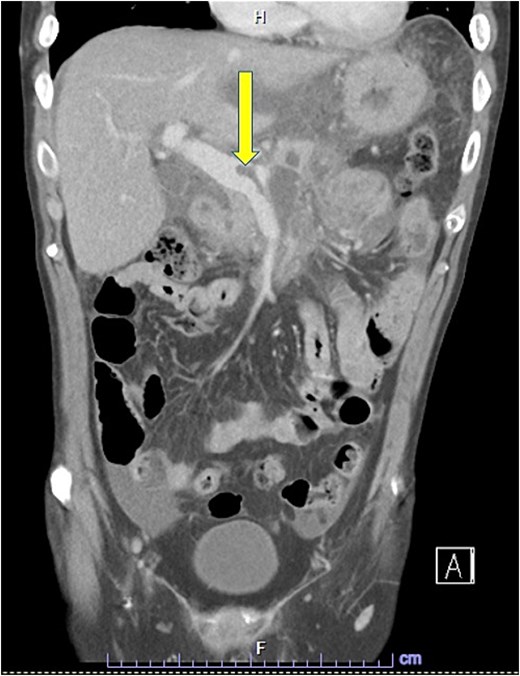

Despite the absence of abdominal symptoms, a computed tomography of the abdomen and pelvis (CTAP) was performed due to markedly elevated lipase levels. The CTAP (Figs 3–5) revealed evidence of acute pancreatitis (Fig. 5, arrow), with a complex peripancreatic fluid collection (Fig. 3, arrow). Additionally, a focal thrombus was observed within the portal venous confluence (Fig. 4, arrow). Further ultrasound of the gallbladder was negative for gallstones (Fig. 6), ruling out gallstone-induced pancreatitis.

CTAP coronal view; focal thrombus within the portal venous confluence (arrow).